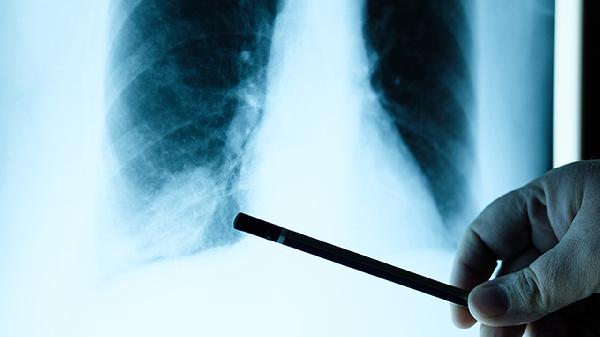

建议肺疾病患者保持室内空气流通,每日进行腹式呼吸训练,饮食宜选择高蛋白、高维生素食物如鱼肉、百合等,避免辛辣刺激。冬季注意保暖防感冒,戒烟并减少厨房油烟接触。适度有氧运动如太极拳可改善肺功能,但急性发作期应卧床休息。定期进行肺功能检查和胸部影像学复查,出现咯血、意识改变等危重症状需立即急诊。